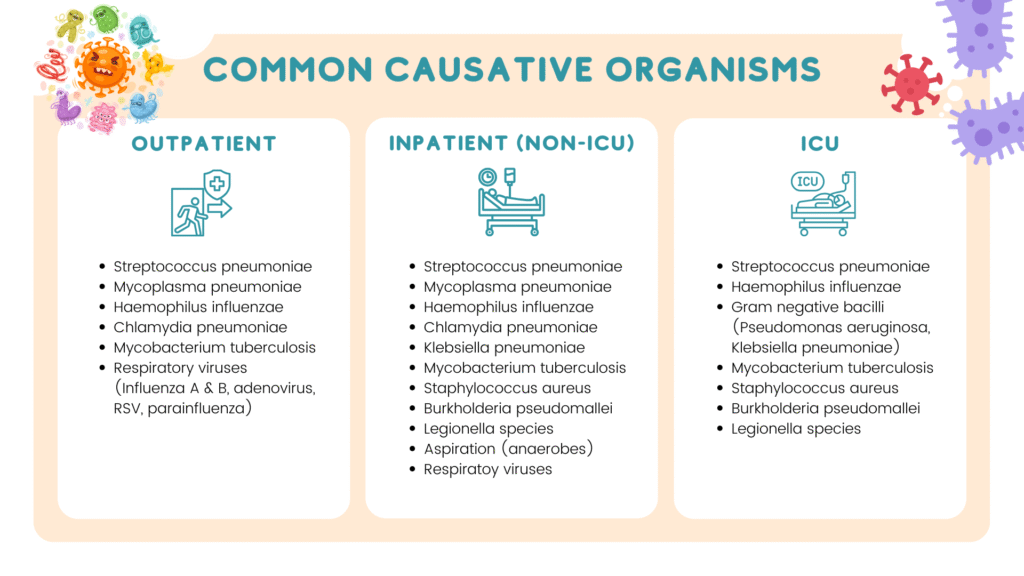

Common causative organisms according to site of care

Burkholderia pseudomallei should be considered especially if the patient has diabetes mellitus.

Gram negative bacilli (Enterobacteriaceae & Pseudomonas may be the cause in those who have had antimicrobial treatment or who have pulmonary comorbitites.

Regarding pseudomonal infection

Strong risk factors

- Prior respiratory infection or isolation of Pseudomonas aeruginosa

- Hospitalization with receipt of IV antibiotics in past 3 months

- Detection of gram-stain rods on a good quality sputum gram stain

Other risk factors

- Recent hospitalization or stay in a long-term care facility.

- Recent antibiotic use

- Frequent COPD exacerbations requiring glucocorticoid/antibiotic

- Structural lung diseases (e.g. bronchiectasis)

- Immunosuppressed.